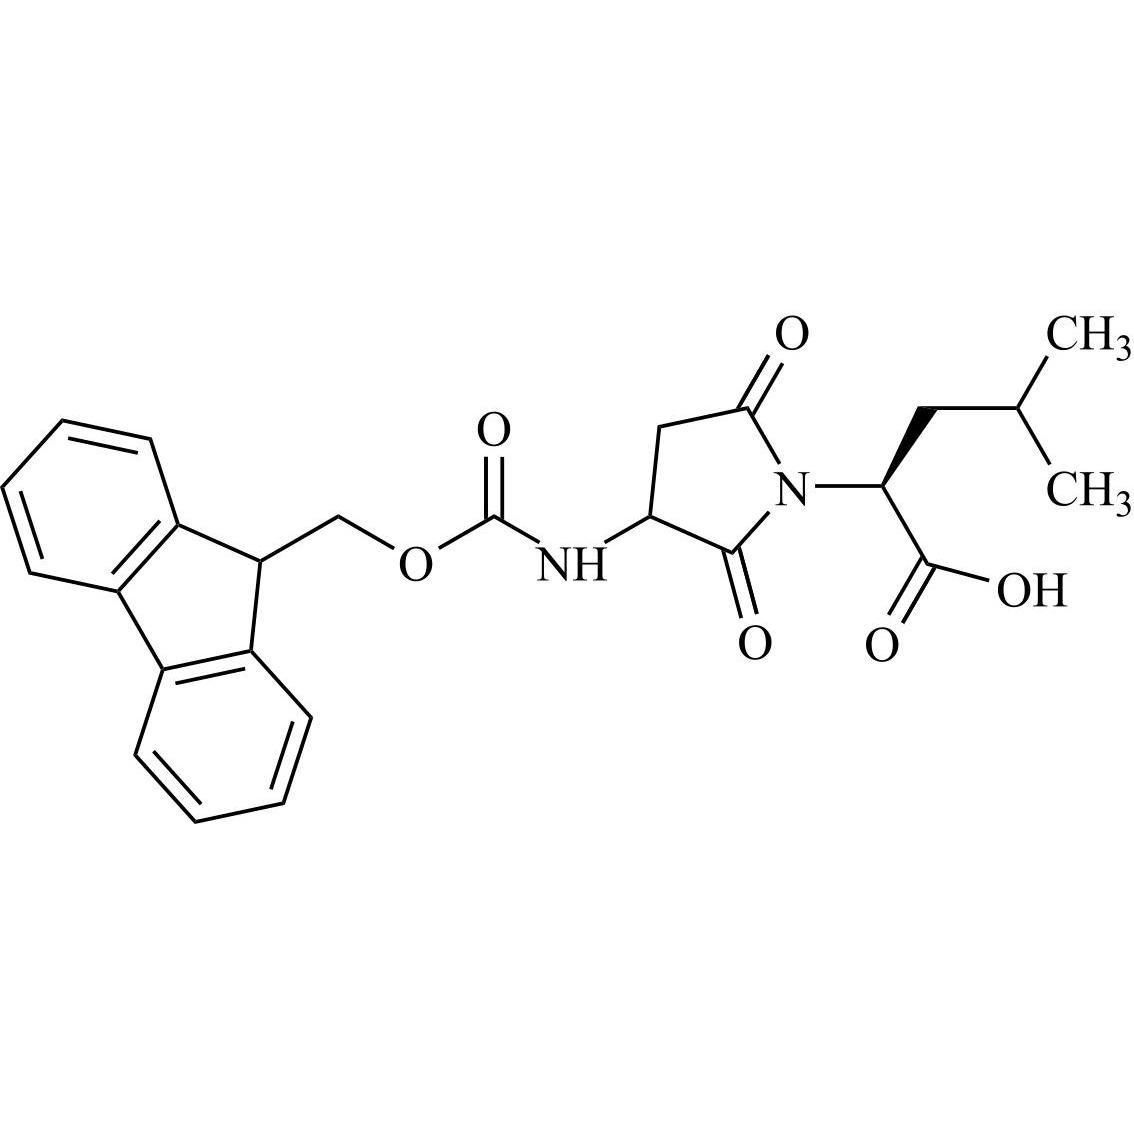

Calcitonin (Salmon) EP Impurity A Tetratrifluoroacetate

M.F.

M.W. 3473.93 4*114.02

CAT# AR-C05767

CAS# NA